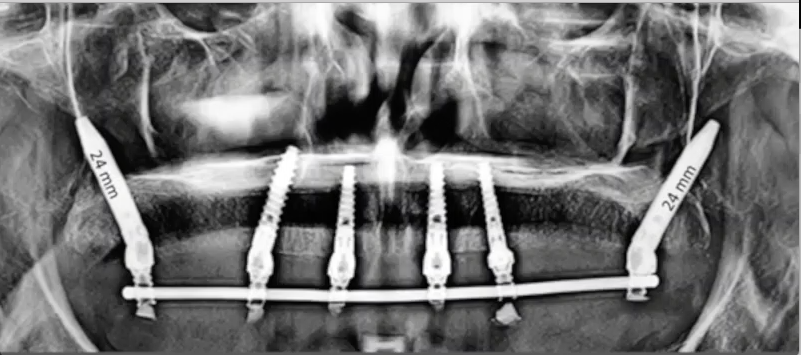

In this case presentation, the patient

suffered from a failed dentition in the maxilla and is planned to be restored with an

implant retained fixed hybrid denture. This video demonstrates the step-by-step

approach of the implant placement in the maxilla, including a titled implant

to avoid the sinus. Plaster impression was taken immediately after surgery and

an immediate temporary metal-acrylic denture was fixed to the implants.